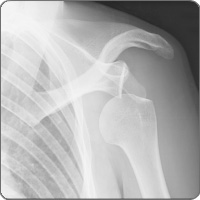

Rotator cuff injury of the shoulder

cond-rotatThe shoulder joint is a ball and socket-type joint formed by the scapula bone (shoulder blade), which acts as the socket, and the head of the humerus (upper arm bone), which acts as the ball. The rotator cuff includes four muscles (supraspinatus, infraspinatus, teres minor and subscapularis) located on the upper back portion of the shoulder. The rotator cuff muscles provide stability to the shoulder joint and perform specific movements at the joint. Injuries can occur as a result of traumatic injury, overuse, incorrect movement patterns involving the arm. A rotator cuff injury can be a muscle strain, a partial tear or a complete rupture of the muscle.